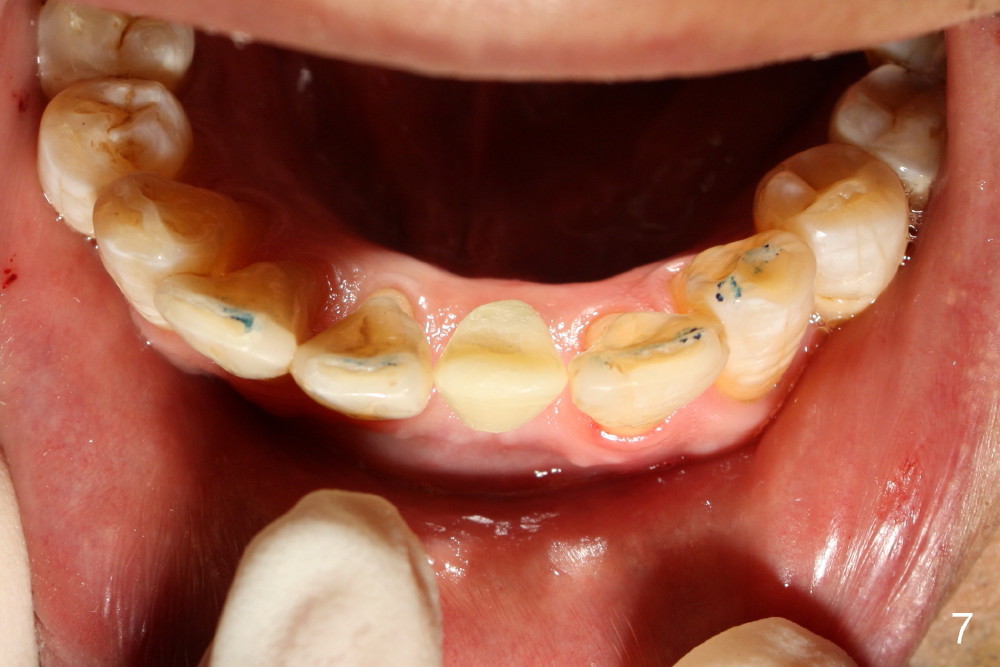

A 3x17 mm one piece implant is planned.  Osteotomy is created by a 1.5 mm pilot drill at the depth of 14 mm without incision (Fig.2); it is close to a neighboring incisor.  The trajectory of the osteotomy is intended to be changed (Fig.3 red) without success (white, 17 mm deep).  With measurement and calculation, the 3x17 mm implant is not expected to touch the root of the adjoining tooth.  In fact it is fine with insertion torque between 50-60 Ncm (Fig.4).  Without incision, the papillae appear to form immediately following implantation (Fig.5).  With adjustment of the abutment (Fig.6), an immediate provisional is fabricated (Fig.7).